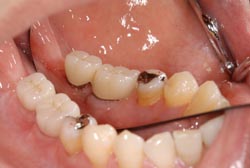

![]() 2次opeがおわり、1ヶ月程たって歯肉の状態がよくなっています。 |

![]() ラボアナログとよばれる器具をつかい歯の型をとっていきます。 技工士さんに型をわたし、上部構造の歯(オールセラミック)を作製します。 |

![]() 技工士によって作製された歯(オールセラミック)です。 |

![]() お口のなかに歯が入ったところです。 この状態で食事をとることができるようになります。 |